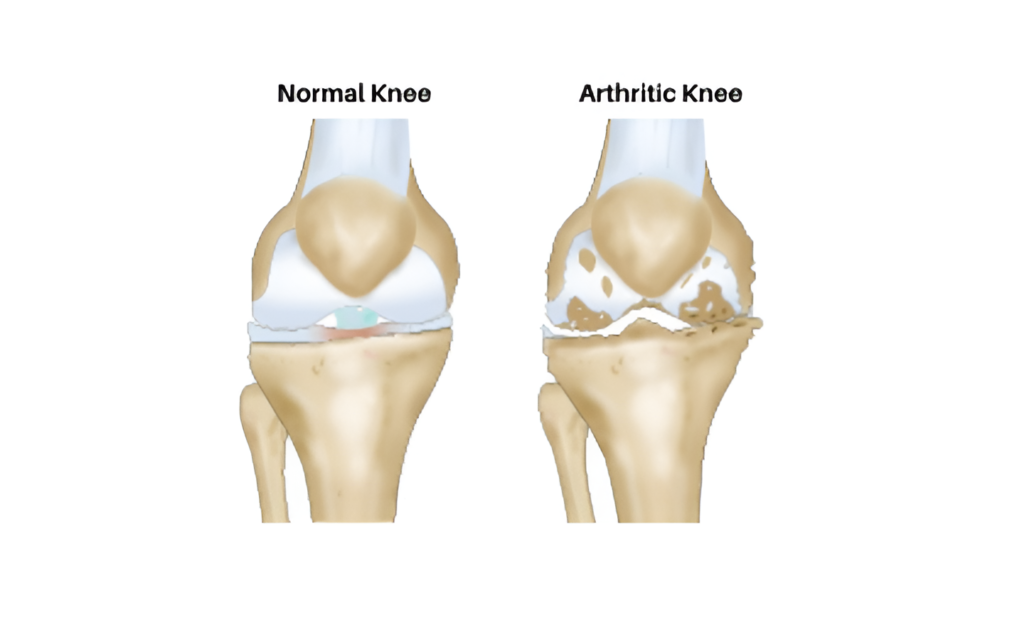

The knee joint is formed by Femur (thigh bone), tibia (leg bone) and patella Damage to the joint is called arthritis and is caused by Obesity, Meniscus tears, Malalignment (“bow-leg”) deformity overloading one compartment, instability (ligament tears) and rheumatological disorders.

Faulty knee alignment (bow-leg or knock-knee) overloads one compartment, resulting in cartilage injury, meniscus tears and joint space narrowing. As the joint space reduces, the alignment also worsens leading to a vicious cycle of joint destruction and deformity. Fortunately correction of the alignment at an early stage can restore knee function and postpone joint replacement